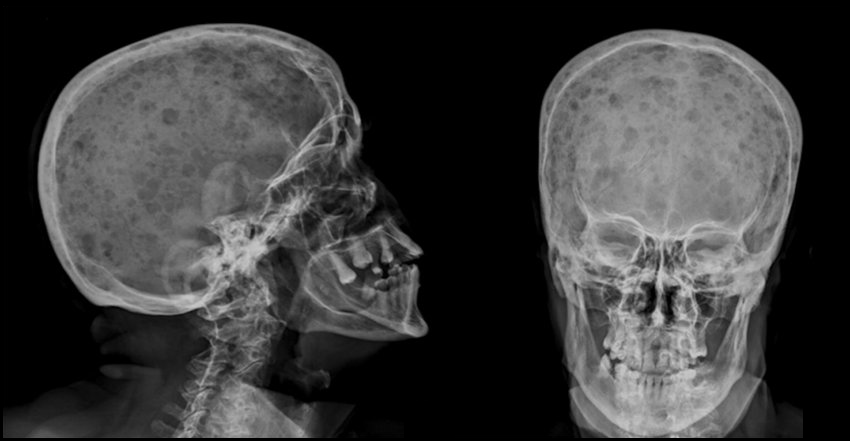

1. Bone lesions

• pain is most common symptom

• osteolytic without osteoblastic zone, e.g. Skull X-Ray

• pathological fractures